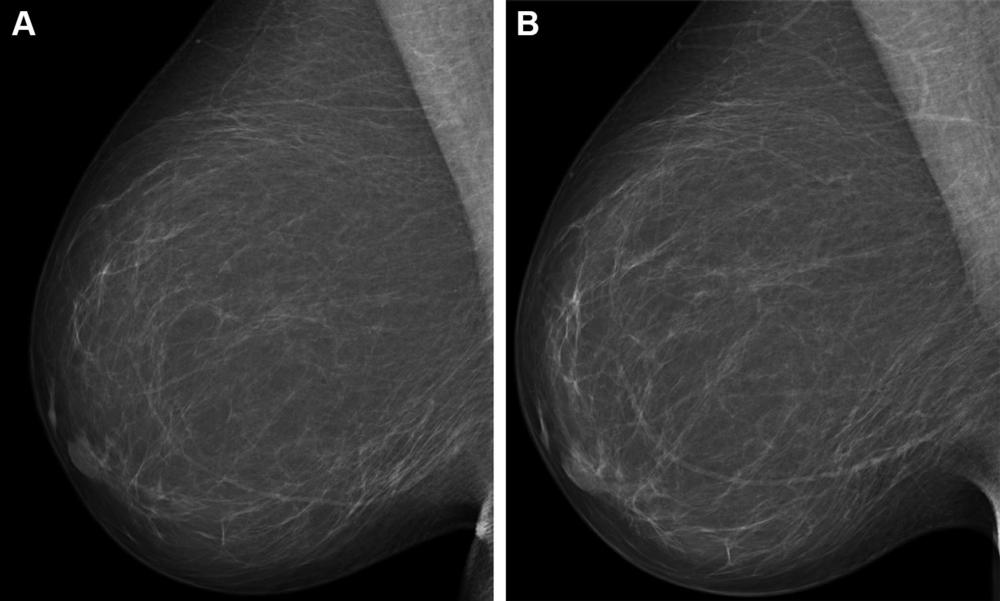

Figure 4. Full-field digital mammograms (right mediolateral oblique view) in a 59-year-old woman show (A) the screening mammogram obtained during the study period and (B) the screening mammogram obtained in the subsequent screening round. The first screening mammogram (A) had a very low combined risk score (lowest 0.1%) as determined by the combination model with texture risk and the examination score. The woman was not recalled and did not receive a breast cancer diagnosis throughout the 5-year follow-up.